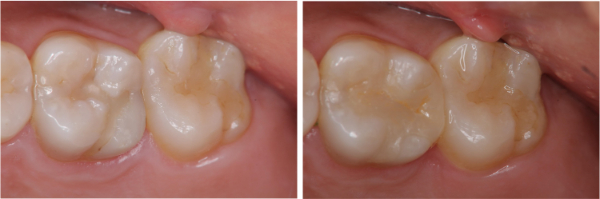

術前、術後比較

陶瓷鑲嵌與陶瓷嵌體因為強度高、抗磨耗,完全不用擔心因長期使用產生耗損、或者因為強度不足,而導致斷裂,讓牙齒又再次蛀牙。陶瓷鑲嵌與陶瓷嵌體可以根據不同的牙齒顏色去選擇顏色製作,又抗染色不會因為時間日久產生變色。

陶瓷鑲嵌與陶瓷嵌體是根據蛀牙的窩洞量身訂做,不管是顏色、精密度都是最佳的選擇,因此是非常美觀與持久的填補窩洞材料與技術。

陶瓷嵌體是根據蛀牙的窩洞量身訂做,不管是顏色、精密度都是最佳的選擇,因此是非常美觀與持久的填補窩洞材料與技術